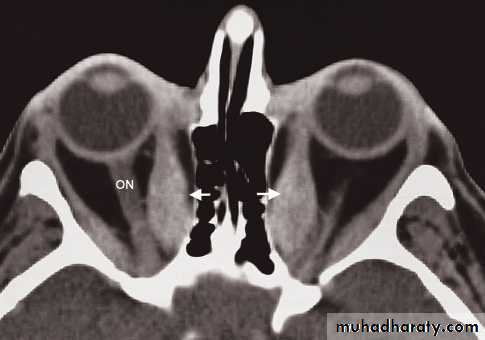

• Computed tomography and MRI clearly demonstrate the anatomy of the orbits.

• To distinguish between masses arising within the orbit, masses arising outside the orbit and thyroid eye disease. With an intraorbital mass, its relationship to the optic nerve can be determined.

• The main causes of intraorbital masses include various tumours, including tumours of the optic nerve, vascular malformations and granulomas.

• In thyroid eye disease, there is enlargement of the extraocular muscles which is frequently bilateral and may affect one, several, or all the eye muscles. There is also infiltration of the fat behind the eye which adds to the exophthalmos.

Blow out fracture

A direct blow to the eye raises the intraorbital pressure and can result in a fracture of the orbital floor, which is the weakest part of the orbit. The break in the orbital floor allows herniation of orbital contents into the antrum,Salivary glands